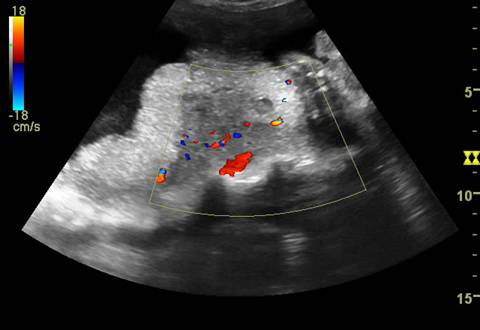

Fig. nr.222. Hematom

la nivelul placii deciduale a

placentatiei la 10 sapt. , cu intreruperea vascularizatiei la Doppler color (

sageata ). Se remarca vascularizatia cordonului ombilical si insertia centrala

a acestuia in placenta

Fig. nr. 223. Hematom retroplacentar ( sageata )relativ recent, hipoecogen ,la o sarcina de 30 sapt. cu DPPNI.

Fig. nr. 224. Acelasi hematom retroplacentar , din figura precedenta. La Doppler Color Flow Map, se remarca semnal in zona respectiva, prin hemoragie activa